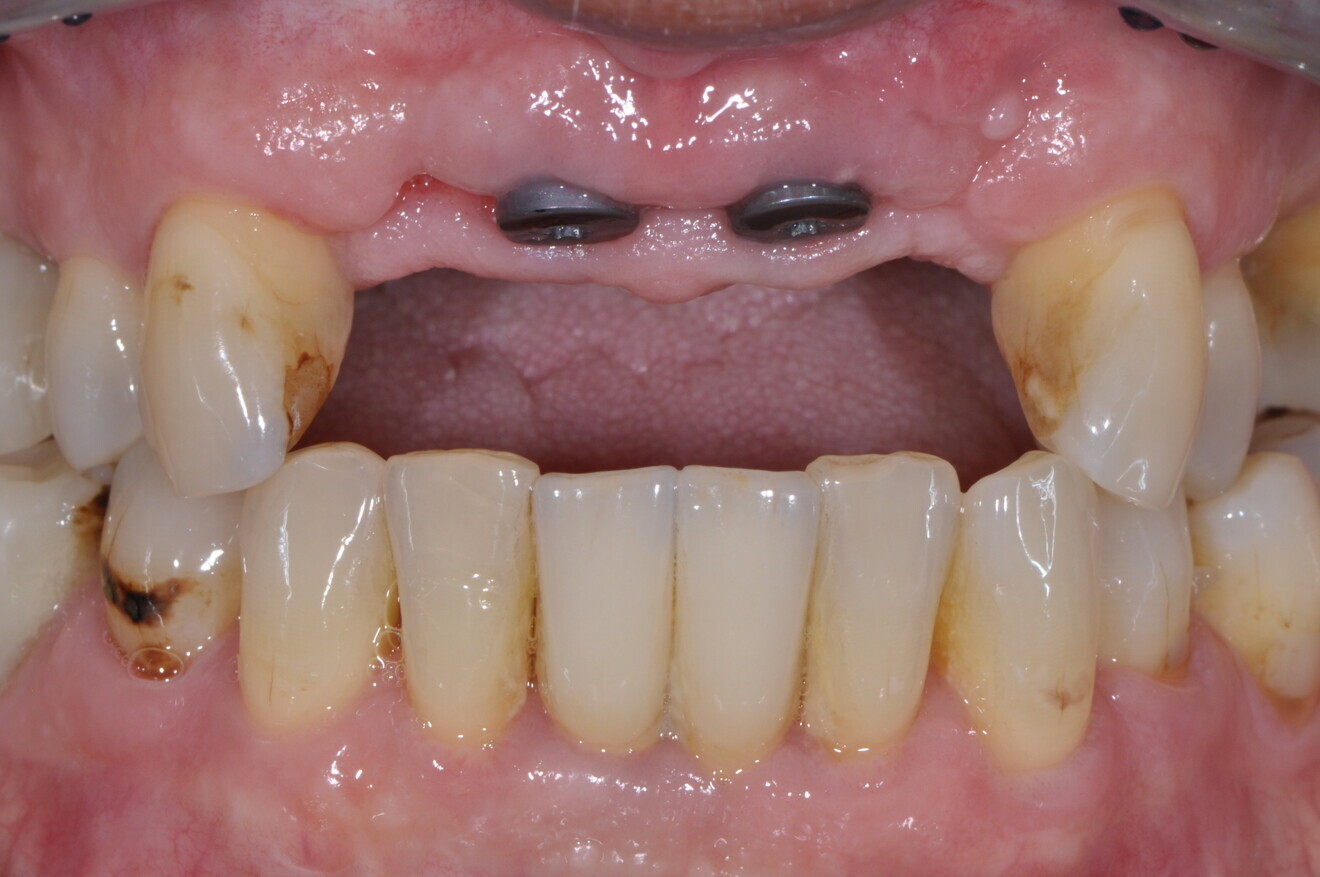

A 62-year-old male patient was referred to my practice for implant planning and treatment in the maxillary anterior region. The teeth in the maxillary anterior region had all undergone endodontic therapy, and teeth #11-22 had received crowns owing to an accident that had occurred 30 years before. The patient reported pain and was conscious that tooth #21 was mobile (Figs. 1a & b).

Fig. 1b: Initial situation.